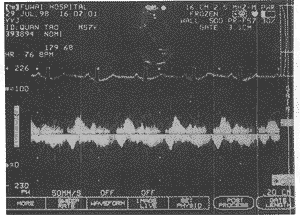

在瘤体颈部可探及收缩期和舒张期出入瘤体的血流信号,从而证实瘤体有 收缩及舒张功能

图3 超声心动图心尖四腔切面:瘤颈部脉冲Doppler信号

特别重要的是本例超声与Doppler检查结果不符,即二维超声显示为假性室壁瘤征象,而Dop pler检查发现“室壁瘤”颈部有收缩期流入左室和舒张期流向瘤内充盈血流频谱,提示“室 壁瘤”有主动收缩和舒张功能,这一点与假性室壁瘤时瘤体无收缩和舒张功能不符,也就构 成了左室肌型憩室的Doppler诊断特征,因此左室异常膨出的颈部若探及收缩期向左室内和 舒张期向瘤体内充盈的血流频谱时,则提示肌性LVD的诊断,因此可与假性室壁瘤相鉴别。